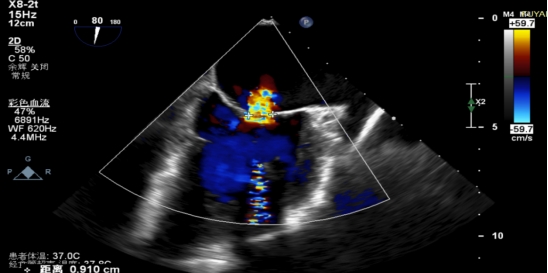

手术当日,在全身麻醉及TEE全程导航下,陈玺全副主任团队凭借丰富的临床经验与精湛操作技巧,顺利完成房间隔穿刺、瓣叶精准定位等关键步骤。针对患者二尖瓣A2/P2 区域反流靶点,团队精准夹合瓣叶,经X-plane技术与三维超声反复确认夹持质量后,成功释放一枚MitraClip XTR夹子。术后即时评估显示,患者二尖瓣反流由术前3 +重度降至轻度,平均跨瓣压仅3mmHg,手术达到预期效果,全程无并发症发生。

术前MR反流

术后平均跨瓣压差3mmHg